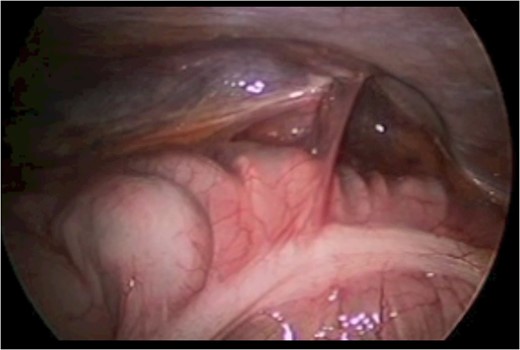

A 43-year-old male patient presented with a right-sided traumatic lumbar hernia after a blunt mechanism. The patient had been pinned between a dirt-mover’s claw arm resulting in a crush mechanism. He sustained injuries to the lumbar spine, sacrum, abdominal wall and 12th rib. On presentation, he did not have clinical or radiographic evidence necessitating abdominal exploration and was observed in a monitored setting. Computed tomography imaging demonstrated a Grynfeltt defect with herniation of the ascending colon and cecum through an area defined by the 12th rib, quadratus lumborum and internal oblique (Figures 1 and 2). After several days of observation and recuperation, the patient continued to have significant pain overlying the hernia site. We electively brought him to the operating room on post-injury Day 4. A laparoscopic repair of the traumatic hernia was performed. Key operative steps included: (i) Wide exposure of the hernia defect via incision of the peritoneum and transversalis as well as mobilization of the ascending colon and duodenal sweep (Figures 3 and 4). (ii) Primary repair of the defect with intra-corporeal suturing of the oblique musculature (Figures 5 and 6). (iii) Placement of an underlay mesh with appropriate redundancy at least 4 cm in all directions around the defect and seating against the iliac crest (Figure 7). Post-operative imaging demonstrates obliteration of the hernia defect and restoration of the abdominal wall (Figures 8 and 9). The patient has recovered, returned to the work force and has no pain or bulge at the repair site 6 months after injury.

With the patient in the left lateral decubitus the herniated right colon spontaneously reduces and the hernia is demonstrated.